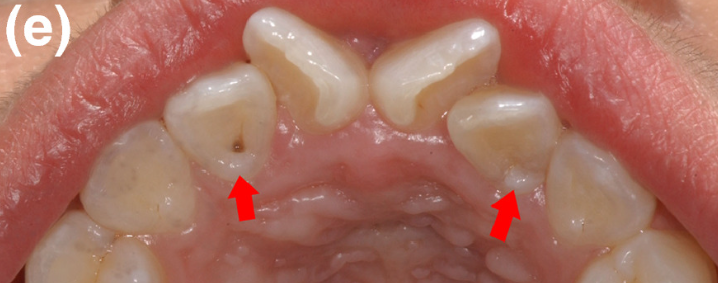

一是,牙齿发生龋坏,俗称虫牙:

二是,牙面色素沉着:

但这两种情况需要齿科医生检查确认,再制订后续计划。

如果是发生龋坏,须先把龋坏去掉,并做充填(补牙)等治疗修复牙齿硬组织。然后,如果这颗牙还存在没龋坏的窝沟,那么可以做窝沟封闭。

如果只是色素沉着,经过适度清洁后可以做窝沟封闭。